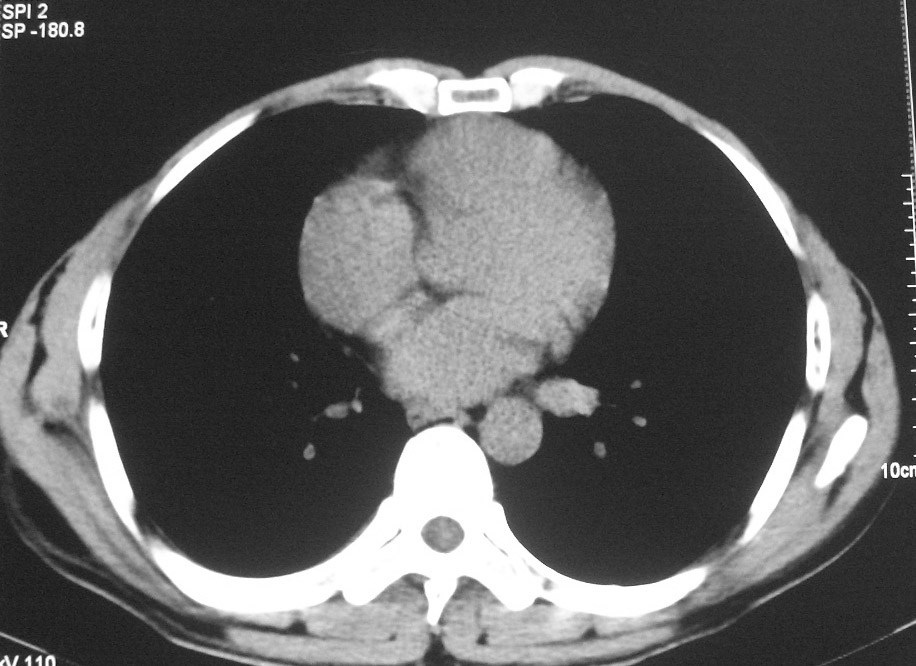

标题: CT5485:[原创]肺部占位请讨论

右肺上叶中央型肺癌并上叶肺不张、纵隔淋巴结肿大

右上叶支气管后壁明显增厚,支持右肺上叶中央型肺癌伴右上叶肺不张、纵隔淋巴结肿大。

右上叶支气管后壁明显增厚,支持右肺上叶中央型肺癌伴右上叶肺不张、纵隔淋巴结肿大。建议支气管镜检查。

右上叶支气管开口变窄,纵隔见肿大的淋巴结。支持右上叶中心型肺癌并右上叶不张纵隔淋巴结肿大。

右肺上叶中央型肺癌并上叶肺不张、纵隔淋巴结肿大.右侧少量胸腔积液。

右上肺中心型肺癌并肺不张,纵膈淋巴结肿大。右侧少量胸腔积液。

右肺上叶支气管后壁增厚,呈鼠尾状狭窄,纵隔内未见明显增大的淋巴结影,考虑为中央型肺癌伴右上肺不张